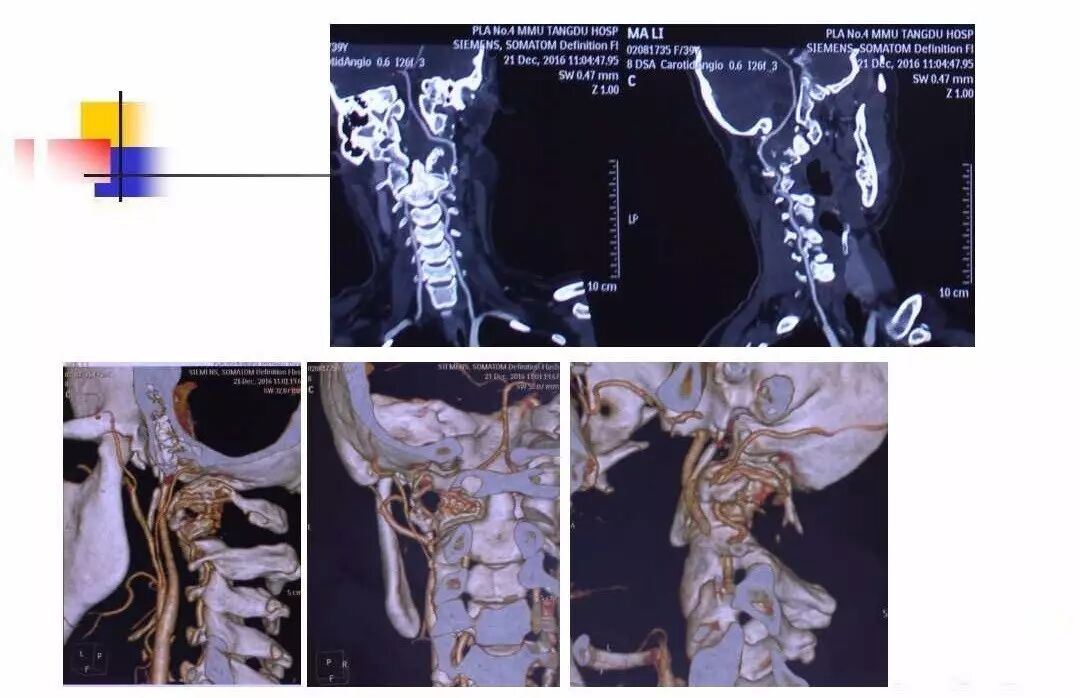

在脊柱神经外科、显微神经外科和颅底肿瘤外科前沿研究和临床诊治领域有着扎实的基础,为全国首批获得脊柱神经外科医师培训认证的神经外科医生。擅长颈椎病、椎管肿瘤及各种脊柱疑难疾病的诊治、脑肿瘤微创手术,尤其擅长颈椎退行性疾病的手术,率先在国内开展了颅底凹陷后路复位、颈前路减压融合等高难度手术,多年来收治了来自全国各地的大量患者,疗效达到国内领先水平。